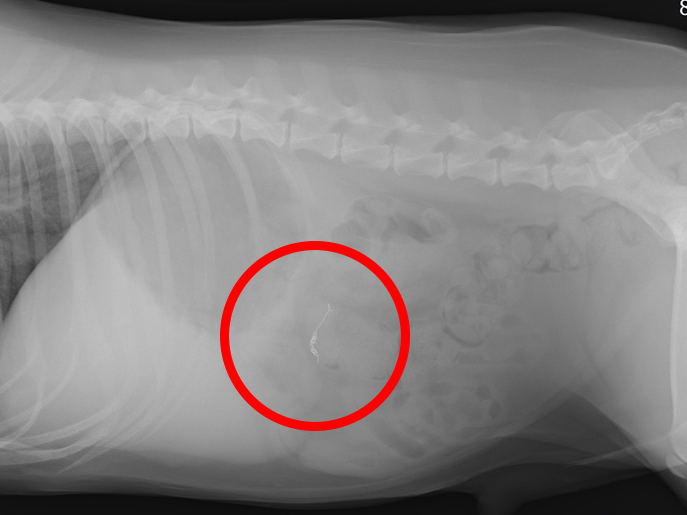

術後2ヶ月後のレントゲン写真(赤丸がコイル)